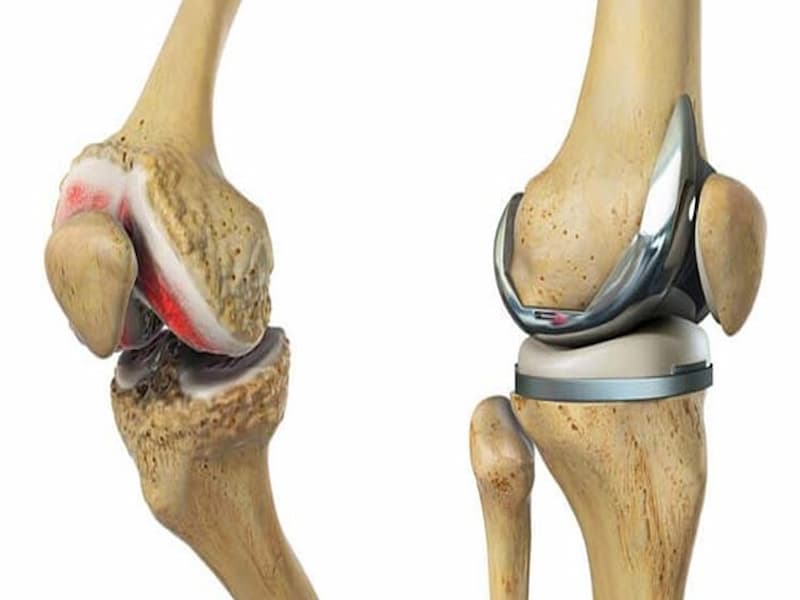

انواع ایمپلنت استخوان پا برای ترمیم شکستگی های صورت گرفته در این اندام استفاده می شود که دارای تنوع زیادی می باشند.

ایمپلنت استخوان پا بسته به شکل طراحی، می تواند در خارج و یا داخل پا استفاده بشود.

از انواع این محصول می توان به میله و میخ، پیچ و مهره، ورق و میله و سیم اشاره کرد.

ایمپلنت استخوانی در شکل های مختلفی طراحی می شود که هر کدام از مواد مختلفی تولید شده است.